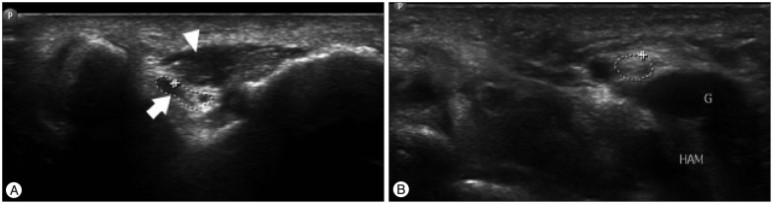

Ulnar Neuropathydueto Cubital Tunnel Syndrome Causedby Anconeus Apitrochlearis : ACase Report 팔꿈치 터널 증후군은 손목 터널 증후군 다음으로 흔히 볼 수 있는 포착 신경병증입니다.이 논문에 나온 환자는 네다섯 손가락 사이에 불쾌감이 있었습니다.통증이 심해지고 팔꿈치 안쪽부터 견갑골 안쪽까지 통증이 계속되었습니다.그리고 손가락 운동이 떨어졌기 때문에 척추 신경 수술을 실시했습니다.ancone use pitrochlearis는 많게는 34%의 유병률을 가진 일반적인 해부학적 변이입니다.(ancone use pitrochlearis : 도르래 위의 낮근) 팔꿈치 터널 뒤쪽을 덮는 근육입니다.상완 삼두근의 연속된 근육으로 척골신경 탈구를 방지하는 역할을 합니다.(척골신경은 팔꿈치신경 중 안쪽을 지나는 신경입니다) 이 부분의 감압술을 통해 통증이 완화되었습니다.도르래상주근은 많게는 34%가 가진 일반적인 해부학적 변이입니다.삼두근 연장으로 척골신경 탈구를 보호합니다.오른쪽 그림의 화살표는 anconeuse pitrochlearis 입니다.MRI 상에서 척추 신경을 억제하고 있는 모습이 관찰이 됩니다.척골신경은 화살촉으로 T2 강조 영상에서 신호가 증가하면서 신경부종이 발생한 모습입니다.(포착증후군에서 초음파를 통해 이러한 신경부종을 관찰할 수도 있습니다.) 그리고 이렇게 계속 누르면 국소적으로 팔꿈치 염증이 생깁니다.

여기서 화살표는 aconeuse pitrochlearis이고 화살표는 척골신경입니다.환자는 수술 후 2개월까지 감각은 개선되었지만 운동 기능은 개선되지 않았습니다.왼손 잡는 능력이 떨어졌는데요.수술 6개월째부터 악력이 회복되기 시작하여 12개월 후에 완전히 회복되었다고 합니다.

Ultra sound Diagnosis of Double Crush Syndrome of the Ulnar Nerveby the Anconeus EPitrochlearis and a Ganglion 척추신경에 의해 신경포착이 발생하는 것은 팔꿈치와 손목에서 가능합니다.이 논문은 doublecrushsyndrome이라고 해서 팔꿈치와 손목 모두에서 포착이 발생한 경우입니다.오른쪽 그림의 초음파를 보면 AE(도르래상주근)에 의해 압박되는 팔꿈치의 척골신경과(cubital tunnel) ganglion에 의해 압박되는 손목의 척골신경을 볼 수 있습니다. (guyontunnel) 척골신경은 주관(팔꿈치)과 가이온터널(손목)로 동시에 압박될 수 있는 이를 doublecrushsyndrome이라는 이 논문의 환자는 오른쪽 손가락의 저린 감각력 부족으로 내원했습니다.(팔꿈치 신경을 누르면 감각 이상이나 운동 이상이 발생합니다) 수술을 통해 팔꿈치의 (anconeuse pitrochlearis) 활차상의 낮근을 감압하고 손목에서 2cm 정도의 ganglion을 제거하였습니다.이 환자는 수술 후 증상이 호전돼 1년간 증상이 없었습니다.